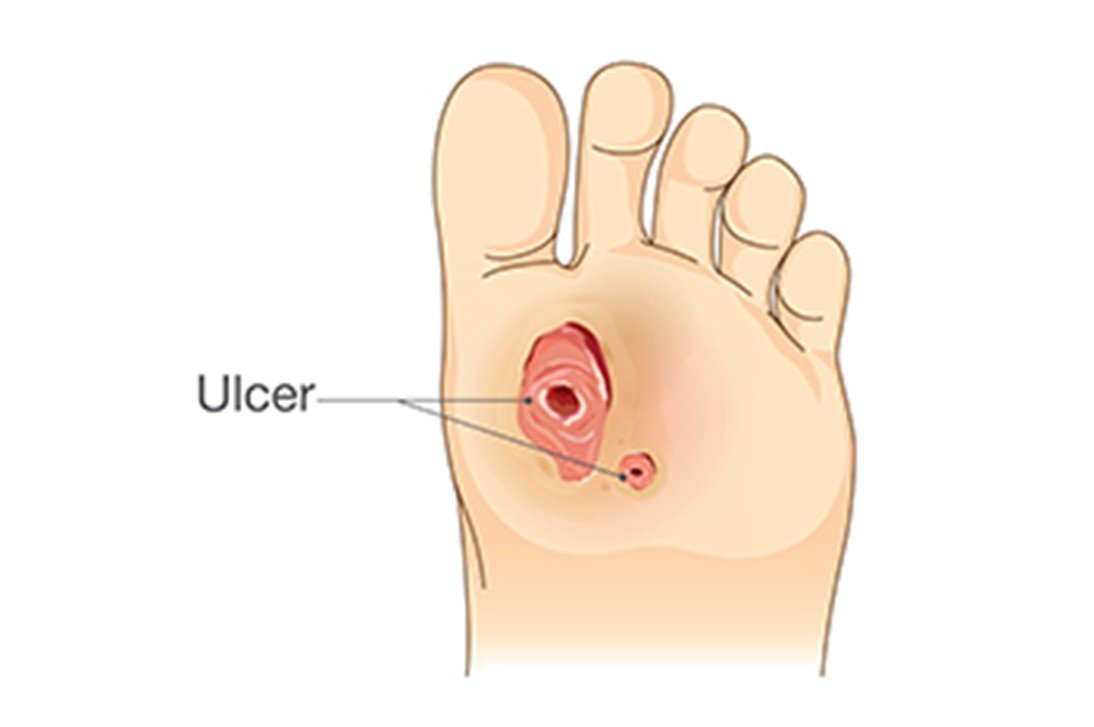

One of the most severe diabetes complications, diabetic foot ulcers. It usually result in infection, hospitalization, and even amputation without appropriate treatment. Treatment is critical to ensure healing, prevent complications, and enhance life quality. This article examines the various management methods of diabetic foot ulcers and the results that patients can attain when managed well.

Understanding Diabetic Foot Ulcers

DFUs are open wounds or ulcers that usually develop on the lower part of the foot in diabetic patients. They ocurr due to diabetes complications like peripheral neuropathy (nerve damage), lack of circulation (ischemia), and infection. These ulcers are severe as they raise the susceptibility of infections. It may result in hospitalization, amputation and severe health complication without treatment.